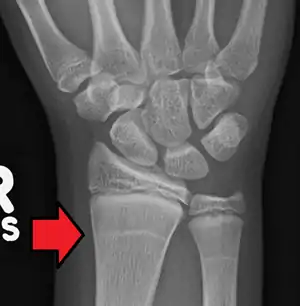

| Growth arrest lines in a child with an underlying bone disease | |